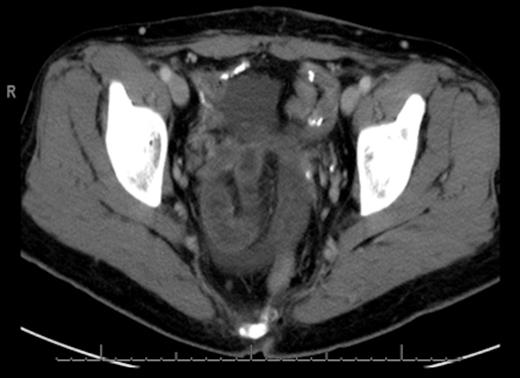

The initial management consisted of a NG tube insertion, IV hydration, and serial abdominal exams. Later, the patient was taken to the operating room due to the significant worsening of her pain. The abdomen was insufflated via the umbilicus with a Veress needle and a 5mm port was placed. Extensive adhesions were visualized throughout the pelvis which was carefully divided. The majority of the small bowel was normal in appearance (Fig. 3), but a segment of 1.5 feet was ischemic and surrounded by dense adhesions (Fig. 4).